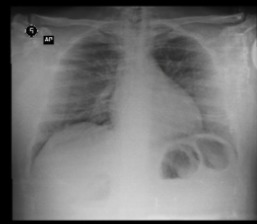

Demanda: Estudo de Caso Clínico (qual o meio de obte-lo: contrato NDA, orçamento?) das análises que fizemos (em anexo) de raio x e tomografia computadorizada obtidos em base pública realizado sob plataforma pública de deep learning com modelo abastecido por datasets públicos de pacientes suspeitos de contágio com covid-19 e outras doenças respiratórias****.

1 - Abrir a plataforma Covid-19, uma base de imagens de raio-X (open data) do Ministério da Saúde de pacientes suspeitos, com resultado POSITIVO para COVID-19, outras doenças respiratórias.

3 - Treinar o Modelo Mellieri Human de Rede Neural Convolucional para detectar o COVID-19 e outras doenças respiratórias em imagens de raios-X e tomografia computadorizada.

4 - Notamos que um paciente pode ter um misto de complicações respiratórias (Covid e Pneumonia por exemplo).

Qual impacto disto nas pesquisas e soluções para combate ao covid-19 como vacinas em função do estágio da doença a exemplo do metadados anexos já que os diagnósticos podem ser únicos para cada paciente no tempo?